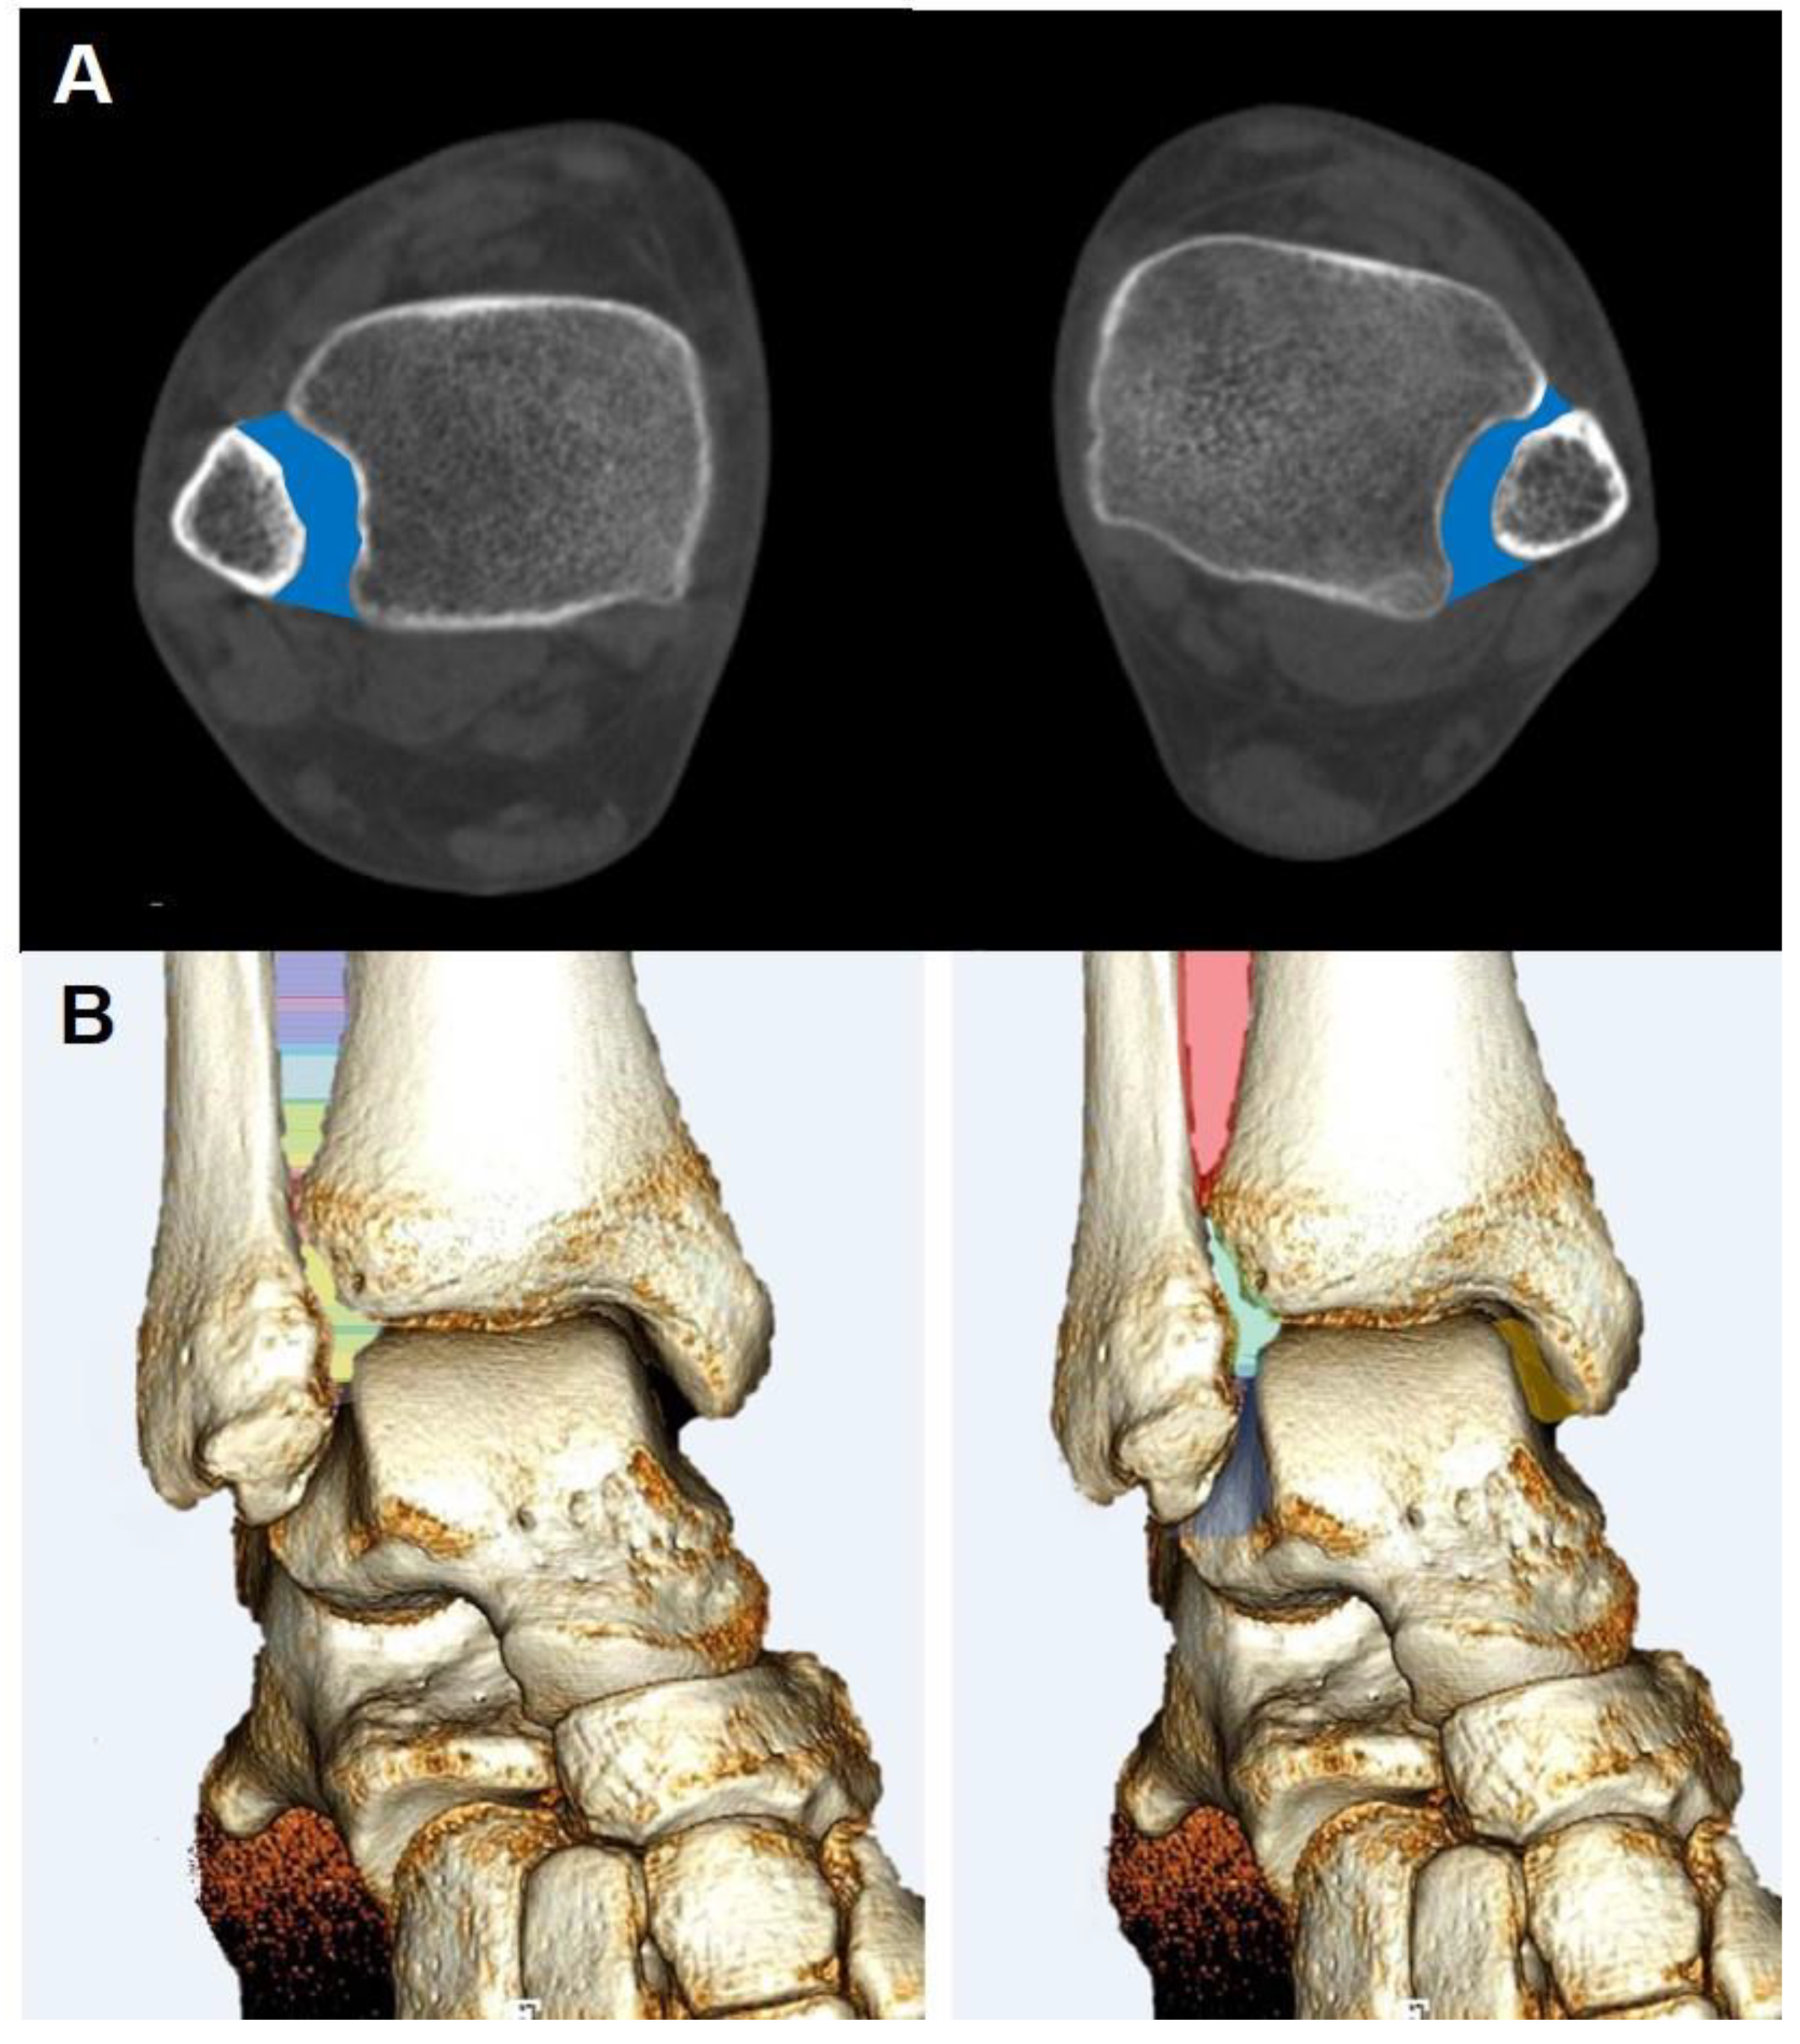

- Syndesmosis injury